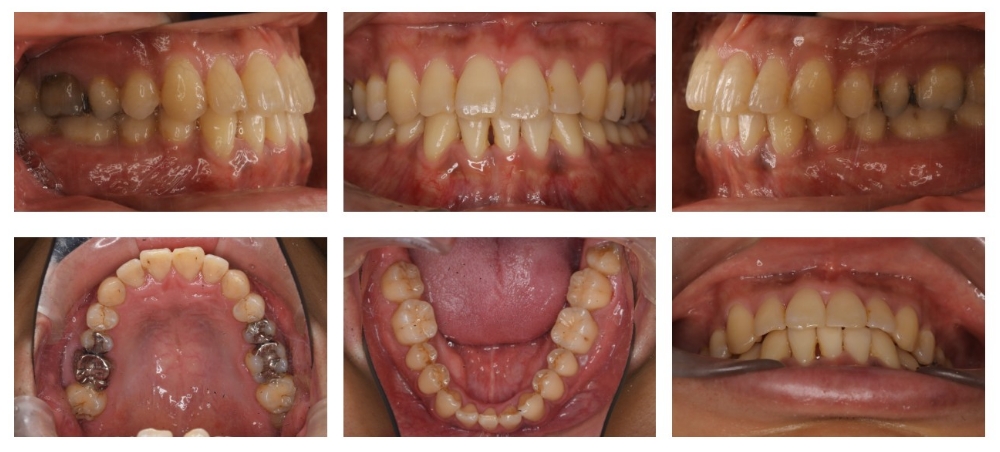

症例

| 主訴 | ガタガタ |

| 年齢/性別 | 30代 / 男性 |

| 抜歯部位 | 非抜歯 |

| 使用装置 | ブラケット(ラビアル) |

| 治療期間 | 1年7ヶ月 |

| リテーナー | 上クリアリテーナー, 下クリアリテーナー |